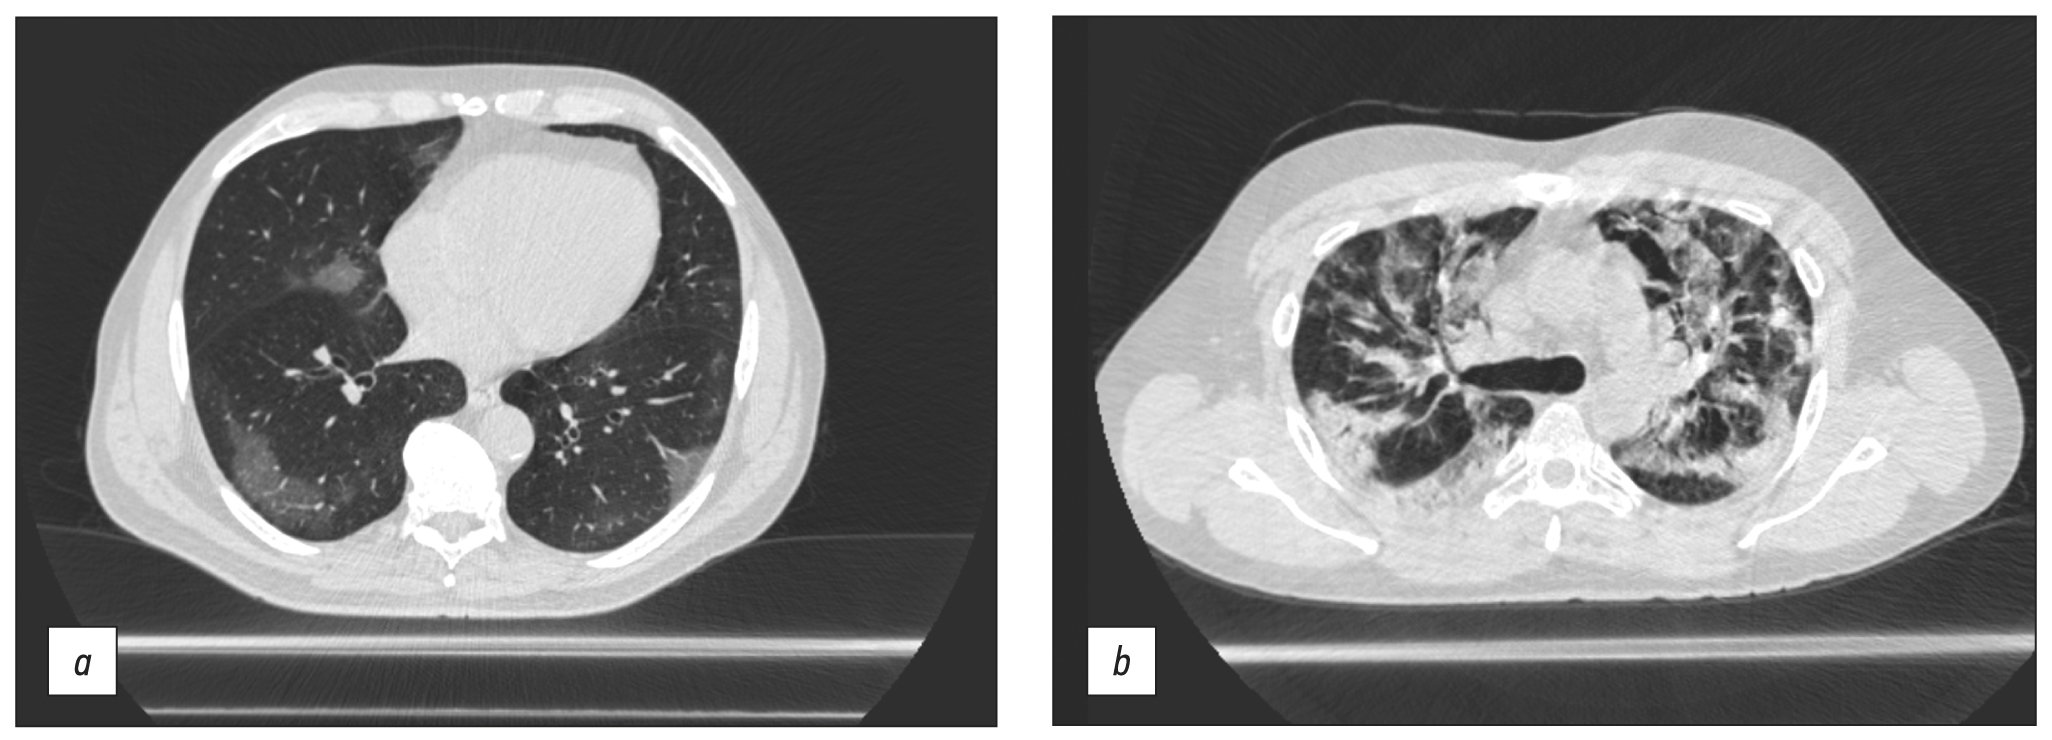

Chest CT was conducted in the majority of cases to obtain a diagnosis or to provide continuing observation for patients with COVID-19 pneumonia. The scanning parameters (Table 1) enable us to obtain images of adequate quality to differentiate between viral pneumonia, cardiogenic pulmonary edema, and bacterial pneumonia. Fig. 5 shows CT data for COVID-19-associated viral pneumonia patients.

Fig. 5. Axial computed tomographic slices of chest organs in the lung window: (a) polymorphic, predominantly subpleural areas of ground-glass opacity, corresponding to the CT image of viral pneumonia (including COVID-19), CT-1, and (b) multiple polymorphic areas of parenchyma compaction with a tendency to merge, with ground-glass opacity areas and mild reticular changes, CT-3.

Long-term (15–25 s) scanning was too long for patients with respiratory insufficiency to remain their breath for the entire examination compared with stationary CT (3–5 s). As a result, motion artifacts (Fig. 6a) and steps (Fig. 6b) were present in CT images produced by breathing motions of the chest (Fig. 6).

Fig. 6. Axial and sagittal computed tomographic slices of chest organs in the lung window: (a) motion artifacts and (b) step artifacts caused by respiratory chest movements during scanning.